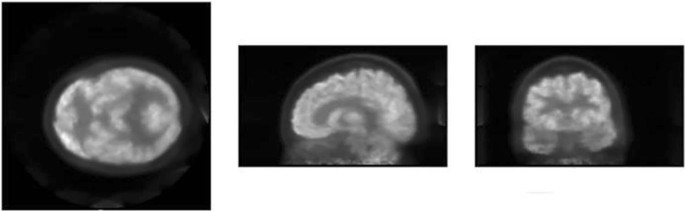

The results for the recovery coefficients were 0.73, 0.78, 1.14 and 1.01 (from smaller to bigger rod diameters) with standard deviations of 45–46% for all rods. The SOR were 0.002 and 0.0001 with standard deviations of 12.3% and 17% for air and water respectively. The patient image is shown in Fig. 6.

Regarding count rate measurements, WB-PETs present a higher NECR peak and lower SF than dedicated brain PETs in all cases, but total count rates are comparable. The scatter detection is related to the system geometry, and smaller gantry translates into greater SF. The NECR curve depends (in the denominator) on the scatter, therefore, its peak is smaller for smaller gantry systems even if the total count rates are similar. The SF for CareMiBrain is in the range of other brain PET systems and NECR and trues peaks are overcome by jPET and G-PET. All systems have used NU 2-2012 phantom for the counting rate performance test and that is the main reason to use it in the present study. Figure 6 shows a patient image from CareMiBrain system, acquired at typical injection activity for a dedicated brain PET study, far below the NECR peak measured. Usually, dedicated PETs work at lower rates than the whole-body systems due to its proximity to the organ of study, allowing a higher frequency of patient monitoring.